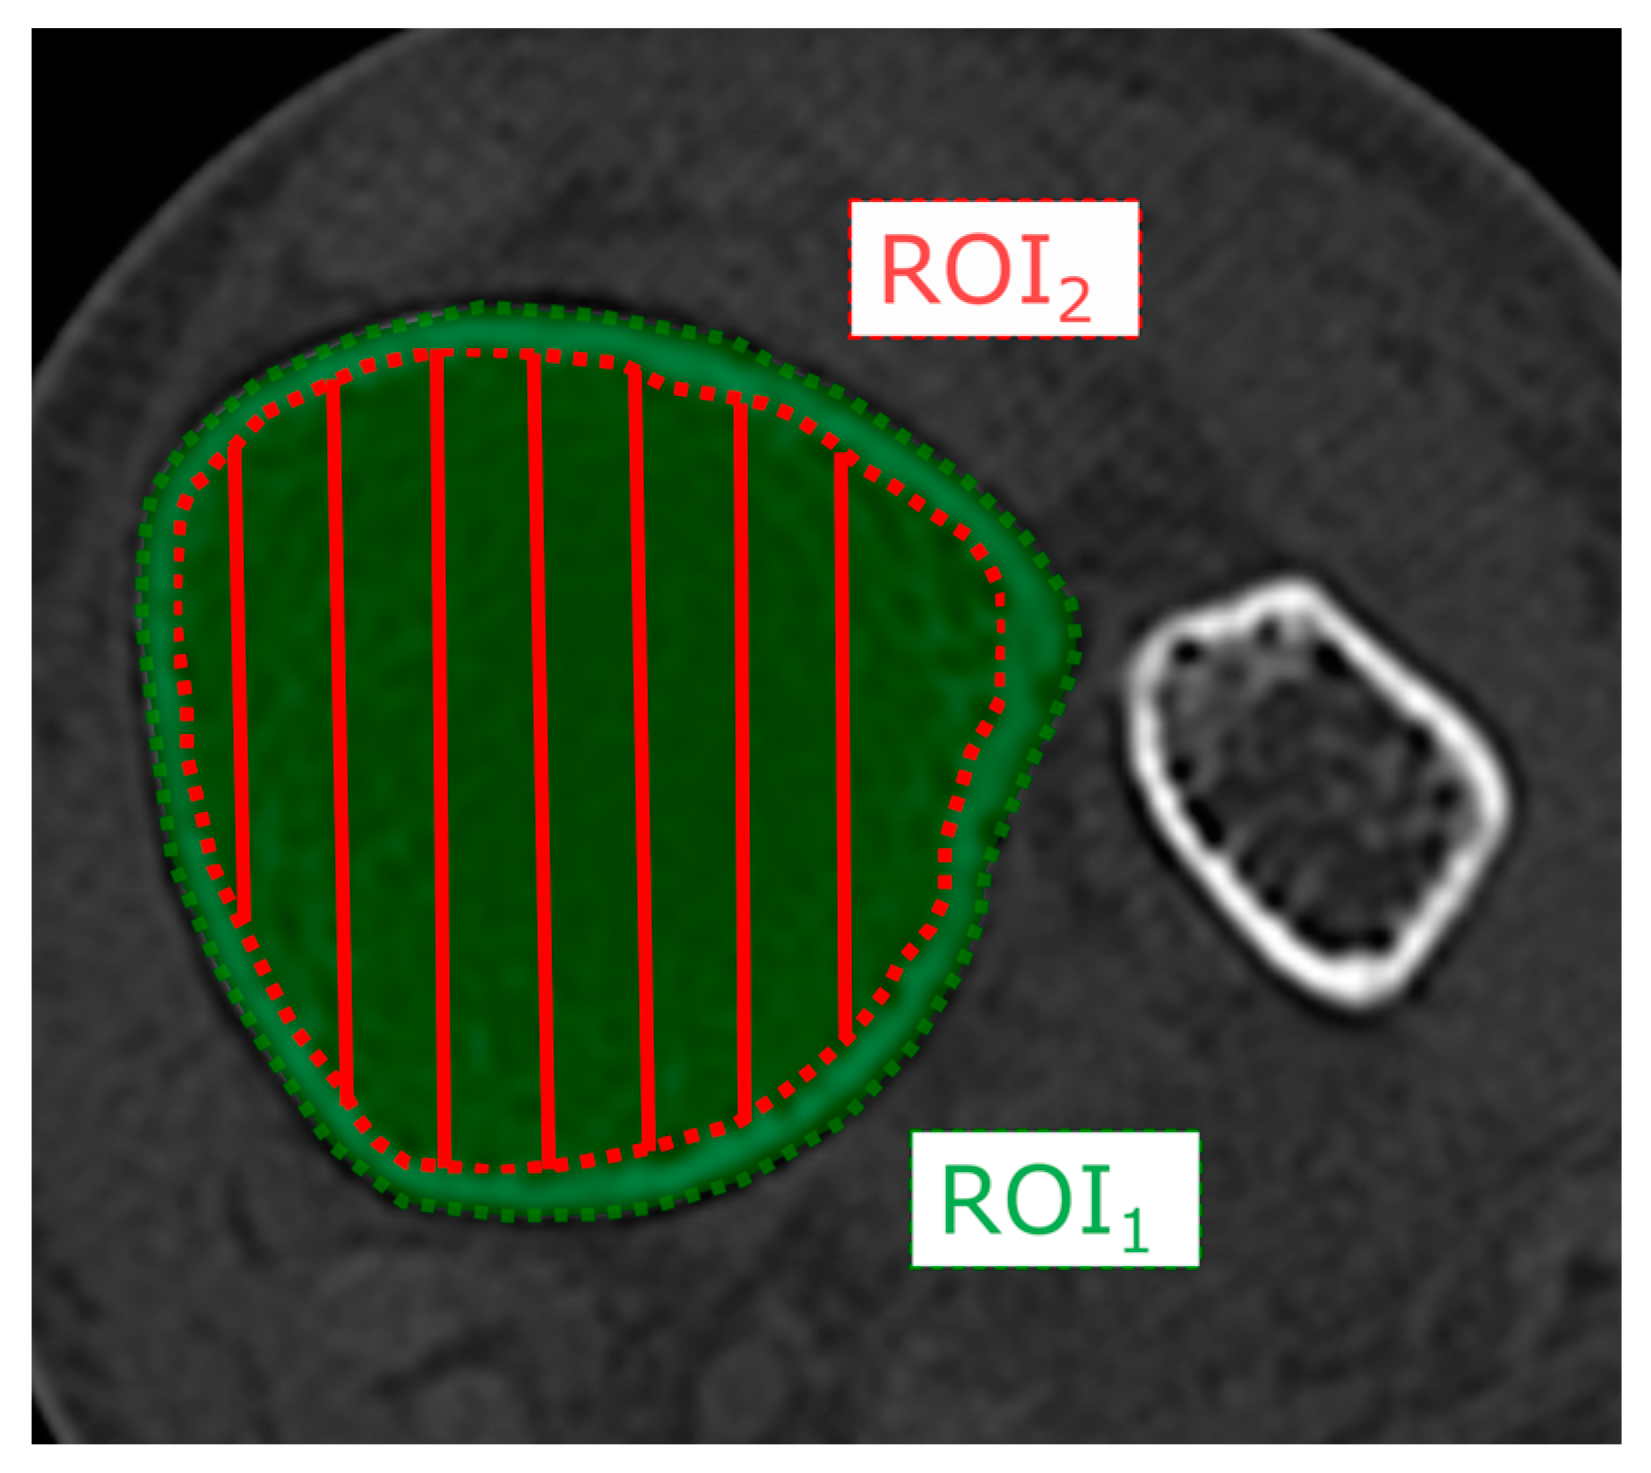

2.2. Radiographic Analysis

3.2. Radiographic Analysis